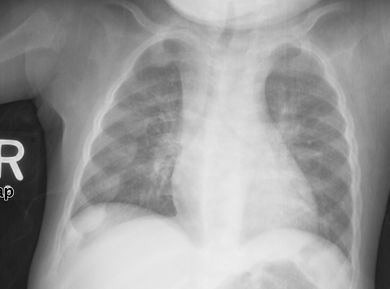

قد يكون الأطفال الصغار قد تقوست أرجلهم وتسمكوا في الكاحلين والمعصمين;[14] قد يصاب الأطفال الأكبر سنًا بالركبتين الروحاء.[11] تقوسات العمود الفقري من جنف حدابي أو قعس قطني قد تكون موجودة. قد تتشوه عظام الحوض . يمكن أن ينتج عن حالة تعرف باسم السبجة الرخادية ناتجة عن تشكل العقيدات على المفاصل الضلعية الغضروفية . يظهر هذا على شكل نتوء مرئي في منتصف كل ضلع في خط على كل جانب من الجسم. هذا يشبه إلى حد ما المسبحة ، مما أدى إلى ظهور اسمها. قد يؤدي تشوه صدر الجؤجؤي[11] إلى وجود تلم هاريسون.

تميل الأشعة السينية أو التصوير الشعاعي لمريض متقدم يعاني من الكساح إلى الظهور بطريقة كلاسيكية: الأرجل المنحنية (الانحناء الخارجي لعظم الساق الطويلة) والصدر المشوه. تحدث التغييرات في الجمجمة أيضًا مما يؤدي إلى ظهور "رأس مربع" مميز يُعرف باسم "caput quadratum".[15] تستمر هذه التشوهات في سن البلوغ إذا لم يتم علاجها تشمل العواقب طويلة المدى التقوس الدائم أو تشوه العظام الطويلة والظهر المنحني[16]

- يظهر التصوير الشعاعي عادة اتساع مناطق التكلس المؤقت للكراديس الثانوية للعظم غير المعدني. عادة ما تظهر التجلف ، والابلاء ، والتفلطح في الكراديس مع النمو وتحمل الوزن المستمر.[37] تُرى هذه التغييرات في الغالب في مواقع النمو السريع ، بما في ذلك عظم العضد القريب ، والزند البعيد ، وعظم الفخذ البعيدة وكل من الظنبوب الداني والبعيدة. لذلك ، يمكن إجراء مسح للهيكل العظمي للكساح باستخدام الصور الشعاعية الأمامية الخلفية للركبتين والمعصمين والكاحلين.[37]